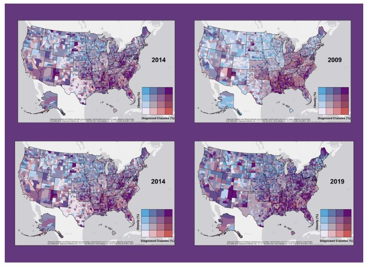

Startlingly, only 12% of American adults maintain the best metabolic health. The National Heart, Lung, and Blood Institute (NHLBI) provides guidelines for identifying metabolic syndrome, which is crucial for understanding its implications, particularly for heart health. The CDC reports an annual healthcare cost of $216 billion dedicated to treating patients with heart disease. The CDC Maps of Diabetes and Obesity demonstrate the escalating rates since 1988, underscoring the urgency of addressing this health crisis. These rising rates are significant compared to the 1988-2012 National Health and Nutrition Examination Survey (NHANES) data. NHANES DATA.

CDC Center for Disease Control and Prevention